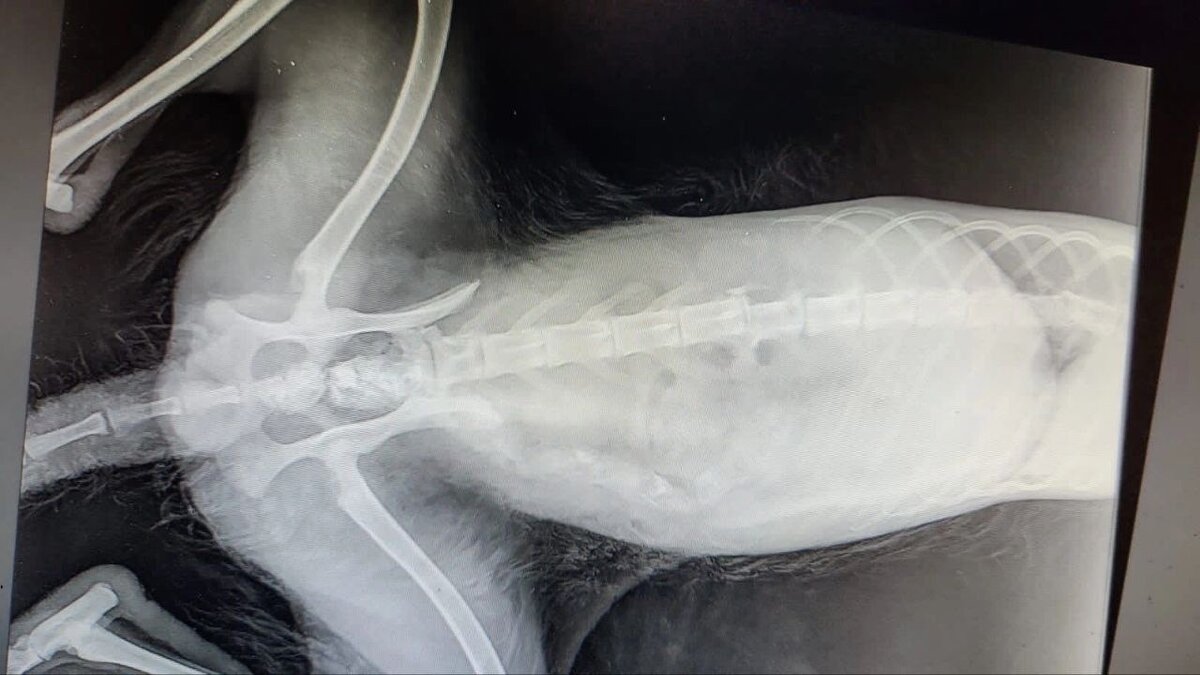

Рентген показал, что у лисы перелом позвоночника, разрыв мочевого пузыря, разрыв селезёнки и разрыв ануса. Травмы оказались несовместимы с жизнью. Вскоре животное издохло.